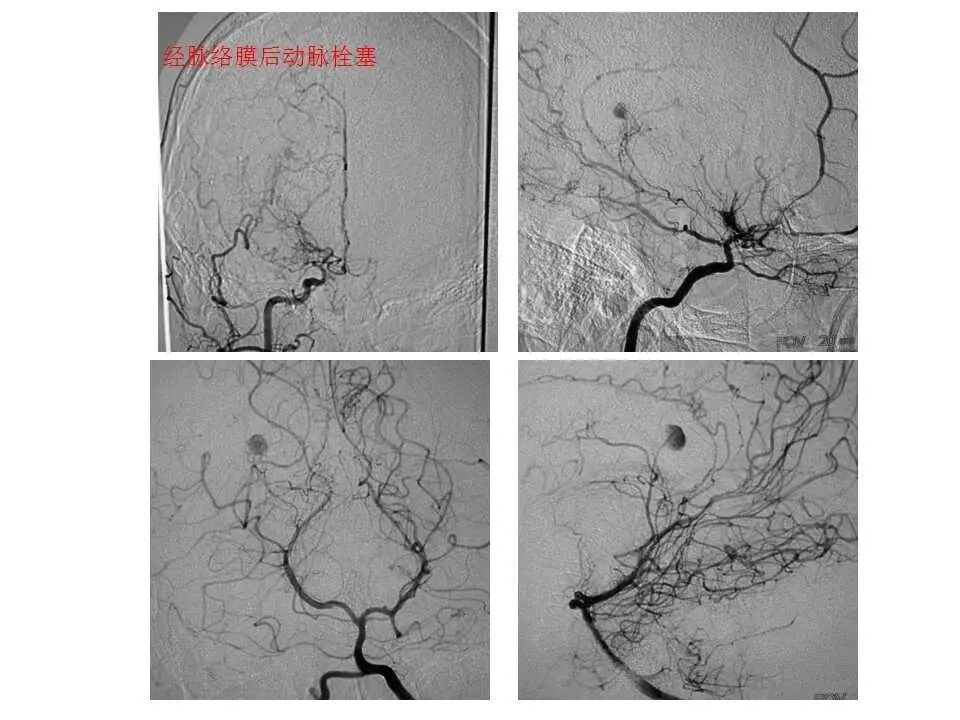

今天为大家分享的是“强生医疗CNV-神经介入专栏”第十五期,由首都医科大学宣武医院何川教授带来的“颅内动脉瘤介入治疗”精彩讲课视频及PPT,欢迎观看、阅读。文章仅代表作者个人观点,如有不同见解,欢迎同道斧正!